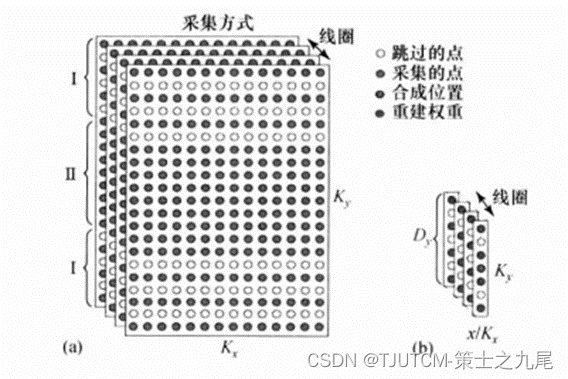

GRAPPA是在AUTO-SMASH和VD-AUTO-SMASH基础上改进的一个并行成像方法。不是从单一测量行合成缺失的K空间行,而是从一组测量行来合成缺失的K空间行;而且在GRAPPA中,合成的是各个单线圈的K空间行,而不是对应全视野的复合的K空间行。

GRAPPA假设是:一个单线圈的K空间中每个数据点都可用所有线圈的K空间邻近数据点的线性组合来代表,并且线性组合权重集在K空间位移不变。

GRAPPA的K空间ACS行数据重建机制,阵列中各个线圈中采集的多块测量行被拟合到阵列中一个单线圈中采集的ACS行(此例中采集的4行数据用于拟合进4号线圈中一个单ACS行,各个圈代表在单一单线圈中采集的数据行)。

GRAPPA是一种基于K空间的重建算法,它以满足奈奎斯特采样定律要求的频率采集K空间中心数据作为自动校正数据(Auto-Calibration Signal,ACS),利用多通道K空间相邻的点线性相关性进行每个通道的K空间欠采样的填充,得到每个通道的全K空间,最后通过通道融合(SOS or ACC)得到最终的无卷褶图像。

为重建K空间中缺失的行数据,需要 分两步进行。第一步是校准,即利用K空间中心附近全采样数据行对重建权重A进行校准;第二步是利用校准的A(具有K空间位移不变性)和已测量的行数据合成高K空间缺失的数据。

(a)GRAPPA数据采集方式。四线圈中每一个K空间数据都是每隔一相位编码行采一行,以加速采集(R=2)。在K空间中心额外采若干ACS行,以形成全采样校准区域(Ⅱ)。高K空间(Ⅰ)是欠采样的,降低因子R=2。

(b)假定采样方式如(a)所示,由GRAPPA产生的重建权重A的空间表象。

目标点总数Nt对于重建来说代表训练例数目。一般来说,训练例数目越大,拟合过程越精确。采更多的ACS行用于增大可利用的训练例数,但以牺牲效率为代价。因为重建是位移不变的,校准可在沿Kx方向所有Nx位置进行,这就进一步增大了Nt。我们称这样的校准策略为“全宽度读出校准”。

原始GRAPPA重建,校准和合成都是在K空间进行的,因此称为“K空间重建”,而且原始GRAPPA重建用的是K空间1D邻居重建。为了提高精度,也可以推广到K空间的2D邻居重建。而且由于系统的线性和FT的可分离性,GRAPPA也可等价地在混合空间(x,Ky)中进行,只要把数据沿Kx进行1DFT,就可以变换进混合空间(x,Kx)中进行,只要把数据沿Kx进行1DFT,就可以变换进混合空间。在混合空间重建时,校准和合成的所有步骤都保持不变,权重系数也一样。对于K空间1D邻居coil-by-coil重建,在混合空间并没有精度或效率优势。然而,推广到K空间2D邻居[Dy*dx]的coil-by-coil重建时,一般是具有精度优势。